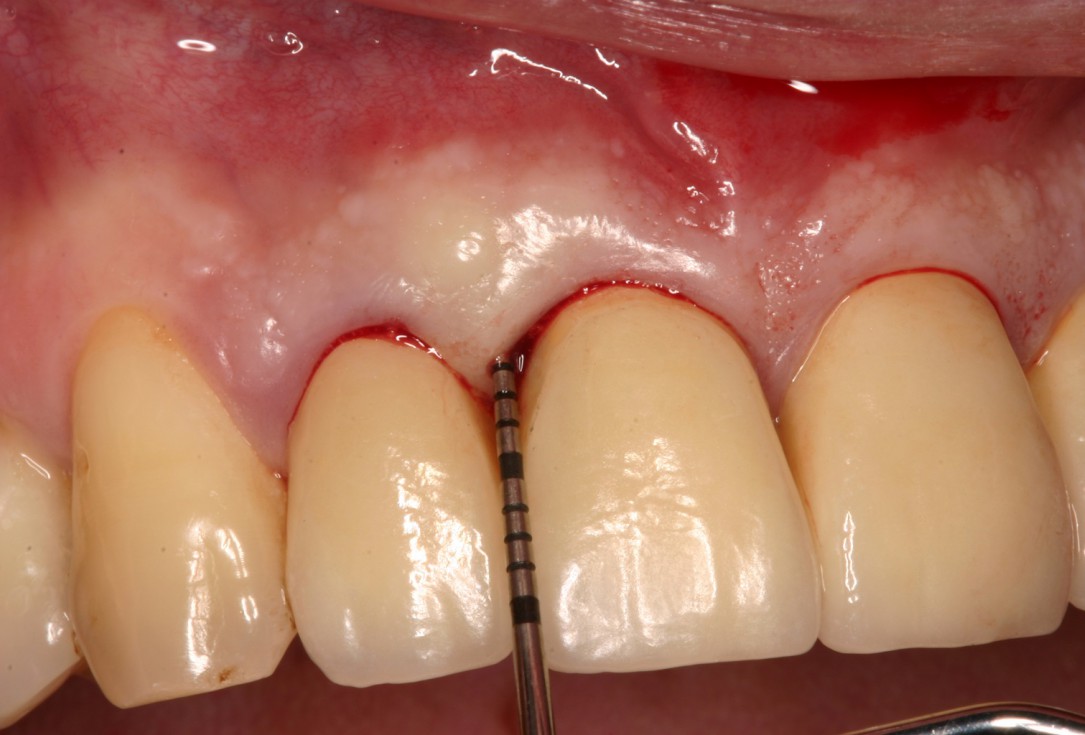

01/08 - Pre-operative probing pocket depth (PPD) at the distal aspect of tooth 11 was 7 mm.Non-contained intrabony defect treated with the simplified papilla preservation flap in conjunction with Straumann® Emdogain® and a particulate bone grafting material - Prof. Dr. Dr. A. Kasaj